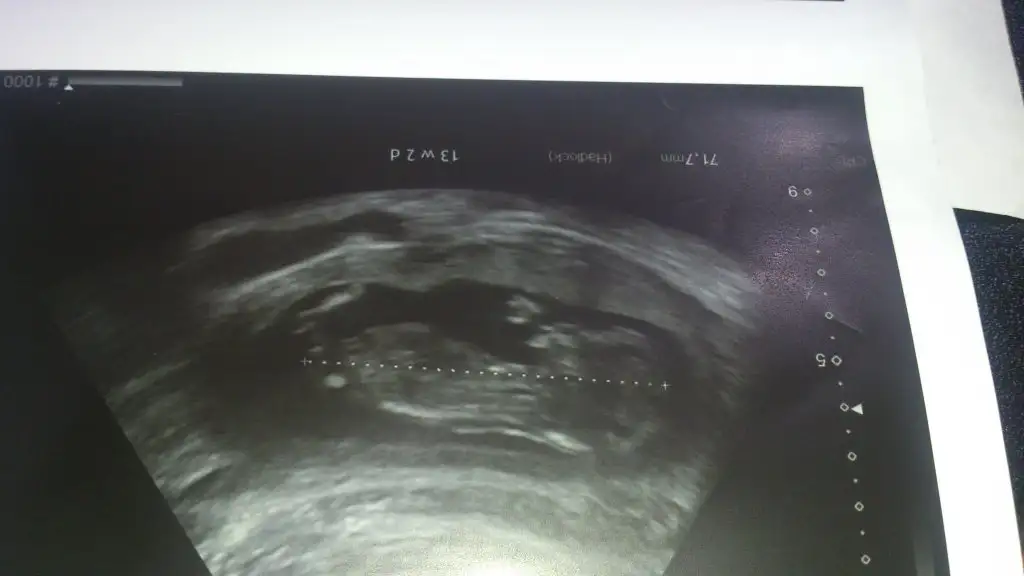

Cnm bu en son foto 13+6, bunada baksana daha net bu foto..Canım ilk fotografa bakmamıştım bebek tam yan değil hafif arkası dönük sidellanın tahmini doğru sanırım...